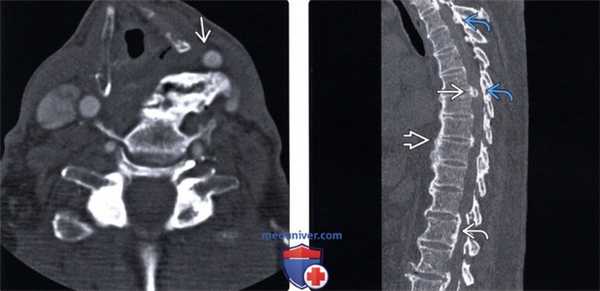

(Слева) КТ, аксиальный срез: массивный спондилофит, оттесняющий левую сонную артерию кпереди и деформирующий левую половину глотки и гортани.

(Справа) КТ, сагиттальный срез, пациент с ДИСГ: множественные очаги новообразования кости: типичная оссификация ППС, а также признаки ОЗПС и кальцификации межпозвонкового диска. Также имеет место и оссификация желтых связок.

(Слева) На аксиальной КТ без КУ у пациента с ДИСГ визуализируется крупный вентральный остеофит с кортикальной пластинкой, оказывающий воздействие на гортаноглотку. При существенном воздействии возможно появление симптоматики.

(Справа) На аксиальной КТ определяется массивная оссификация со смещением левой сонной артерии и воздействием на гортаноглотку слева. Расщелина в оссификате на уровне межпозвонкового диска - частая находка. Возможна сопутствующая дисфагия, обусловленная не только механической обструкцией пищевода, но и воспалением и фиброзом.

(Слева) На аксиальной КТ в костном окне определяется ОЗПС в сочетании с ДИСГ. В самых верхних отделах ОЗПС выглядит как пальцевидное выбухание, обычно не контактирующее с позвонком.

(Справа) На аксиальной КТ в костном окне определяется выраженная оссификация ЗПС в основании С2, сливающейся с задней кортикальной плааинкой позвонка. Результирующее сужение позвоночного канала приводит к тяжелому сдавлению спинного мозга и симптомам миелопатии, наличие которых является одним из немногих показаний к хирургическому вмешательству.